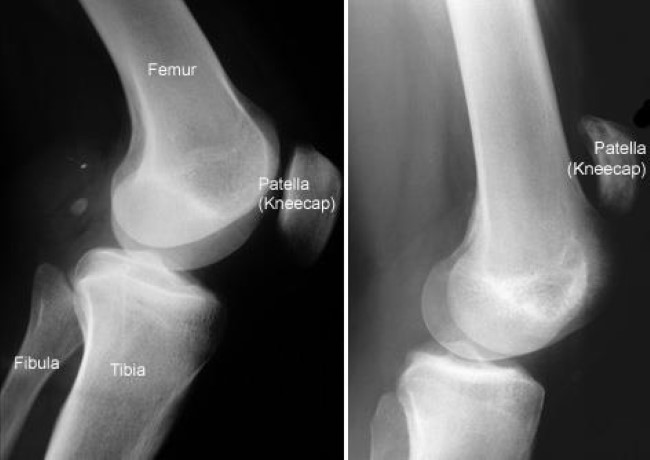

This injury is most commonly due to an abrupt, forcefully impact on your thigh. Tendon tear in the elderly is usually caused by a medical condition like gout or a thyroid disorder. It can cause joint pain, stiffness. This type of tear is also caused by falls, direct force to the front of the knee. Patellar tendon rupture is a tear of the tendon that connects the knee cap (patella) to the tibia.

Peroneal tendon subluxation | eorthopod.com. It usually requires surgery and physical therapy to. In part 2 of building your legs, coach clint greffard goes into detail about his quad tendon tear, the surgery, and recovery process. Often there is sudden onset of pain and walking is difficult. Patellar tendon rupture is a tear of the tendon that connects the knee cap (patella) to the tibia. The peroneals are two muscles attaching along the outer edge of the lower leg. A pop may be felt when it occurs. In a partial tear, the tendon is partly torn but still joined to the calf muscle.

A large tear of the patellar tendon is a disabling injury. A tendon injury may seem to happen suddenly, but usually it is the result of many tiny tears to the tendon that have happened over time. A quadriceps tendon tear often occurs when there is a heavy load on the leg with the foot planted and the knee partially bent. Treatment for quadriceps tendon tear: Quadriceps tendon tear is an injury that occurs when the tendon that attaches the quadriceps muscle (a group of 4 muscles in the front part of the femur). Peroneal tendon subluxation | eorthopod.com. This type of tear is also caused by falls, direct force to the front of the knee. It usually requires surgery and physical therapy to.

A large tear of the patellar tendon is a disabling injury. This type of tear is also caused by falls, direct force to the front of the knee. Your tendons are under a lot of tension when you exercise, especially when you do explosive activities like sprinting and jumping. Patellar tendon tears are a relatively common and severe tendon injury. An achilles tendon tear occurs when the tendon attaching the calf muscle to the heel is completely torn. Tendonitis is when a tendon swells (becomes inflamed) after a tendon injury. Quadriceps tendon tear is an injury that occurs when the tendon that attaches the quadriceps muscle (a group of 4 muscles in the front part of the femur). In a complete rupture, the ability to extend that knee is decreased. Tendonitis is the swelling of a tendon, which is a thick cord attaching a muscle to a bone. A supraspinatus tear is a tear or rupture of the tendon of the supraspinatus muscle, which is located at causes. A tendon is the fibrous tissue that attaches muscle to bone in the human body. In a partial tear, the tendon is partly torn but still joined to the calf muscle. A bicep tendon tear can occur in long head of biceps or distal end of biceps.